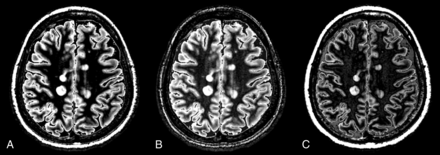

The parameters for creating synthetic DIR images were optimized for each patient by adjusting the second TI to intensify the contrast between MS plaques and WM (Fig 1). All other parameters were the same for each patient, as follows: TR, 15,000 ms; TE, 100 ms; and first TI (TI1), 3750 ms. The second TI (TI2) was selected to suppress the WM and CSF signals while maximizing the GM signal, in accordance with the method of Gabr et al.25 This procedure was accomplished by minimizing the following expression:

An example of DIR optimization. A DIR image with a second TI of 460 ms (A) (as determined according to the equations in the main text) shows better delineation of MS plaques than a DIR image with a second TI of 360 ms (B) or 560 ms (C).

Here, T1, T2, and PD of each tissue type were averaged from the following ROIs (3 × 3 voxels, corresponding to 2.25 × 2.25 mm2): CSF, bilaterally in the anterior horns of the lateral ventricles; GM, bilaterally in the thalamus, occipital cortex, and frontal cortex; and WM, in the corpus callosum—one in the genu and another in the splenium—and bilaterally in the centrum semiovale. The second TI of each image fell in the range of 460–480 ms after optimization of the synthetic DIR images for each patient.